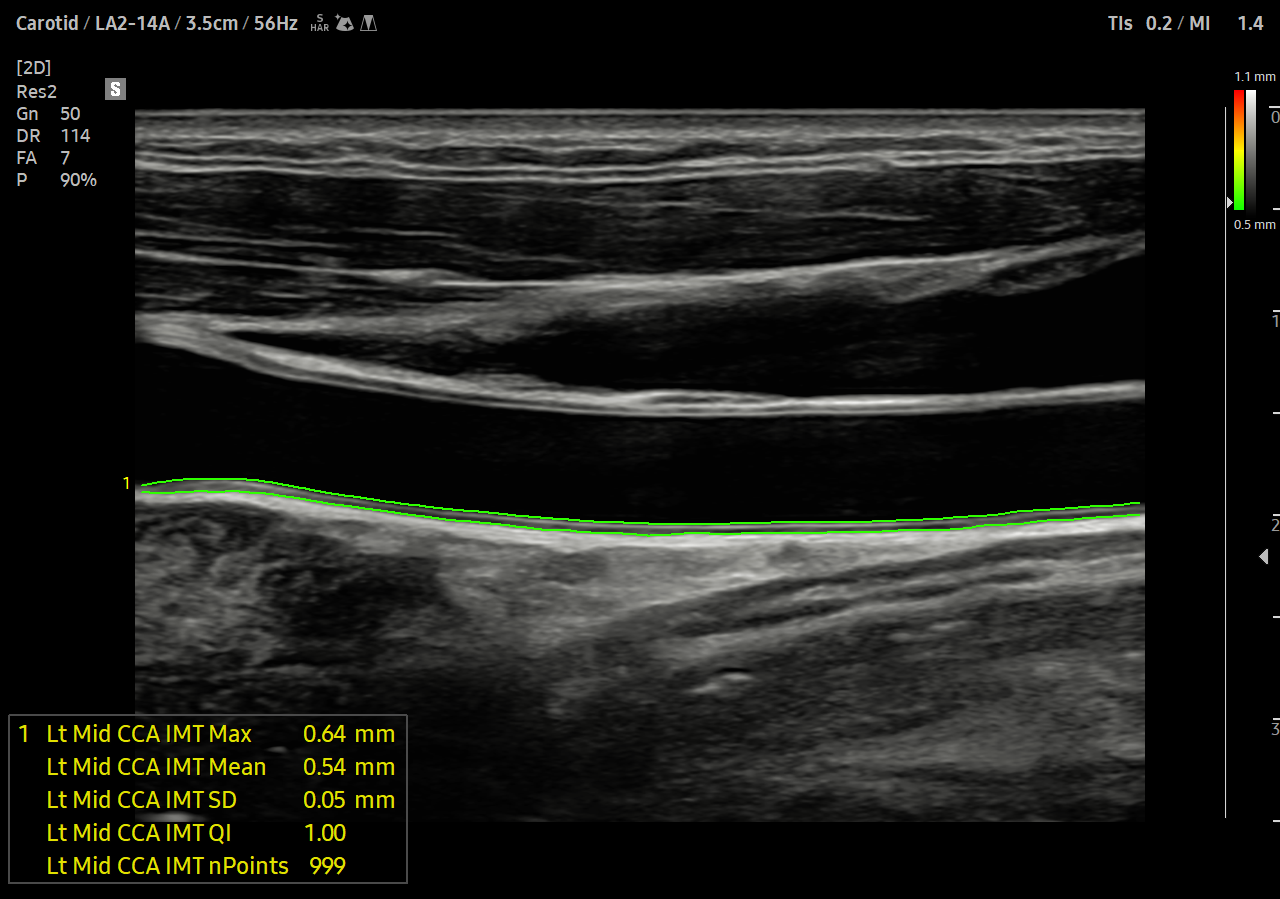

Měření tloušťky intimy a medie jediným kliknutím

AutoIMT je screeningový nástroj pro analýzu potenciálního rizika kardiovaskulárních onemocnění pacienta. Umožňuje snadné měření tloušťky přední i zadní stěny intimy a medie krční tepny pouhým stisknutím tlačítka.